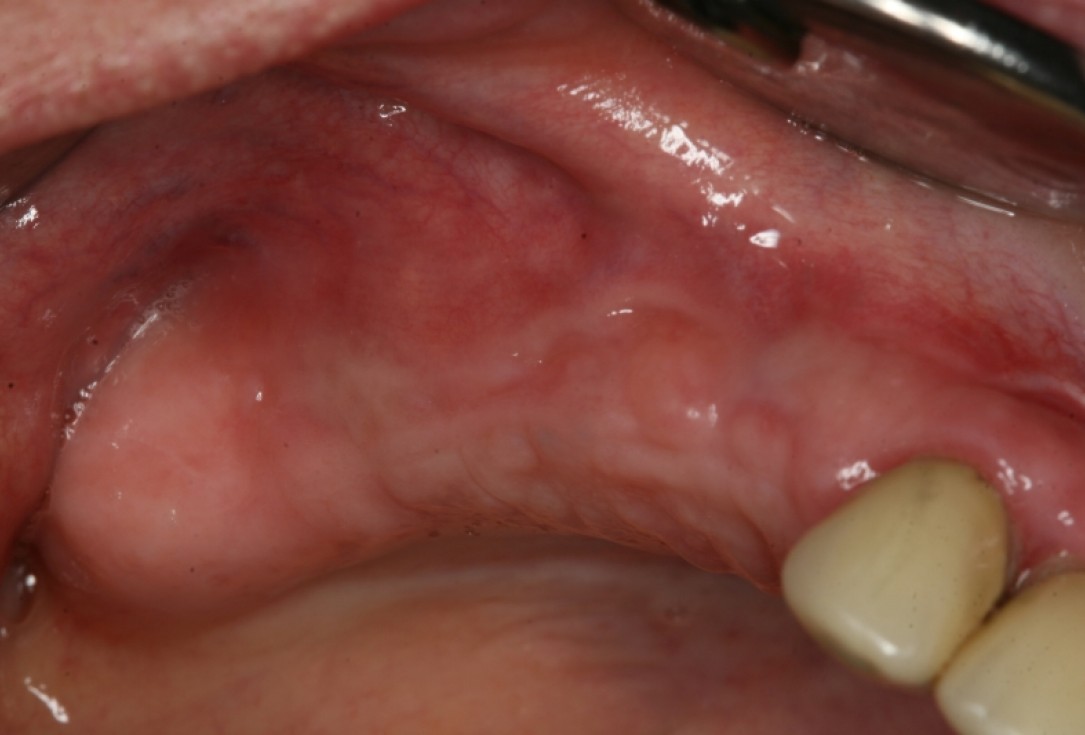

Initial clinical situation with gum recession and labial bone loss eight weeks following tooth extraction